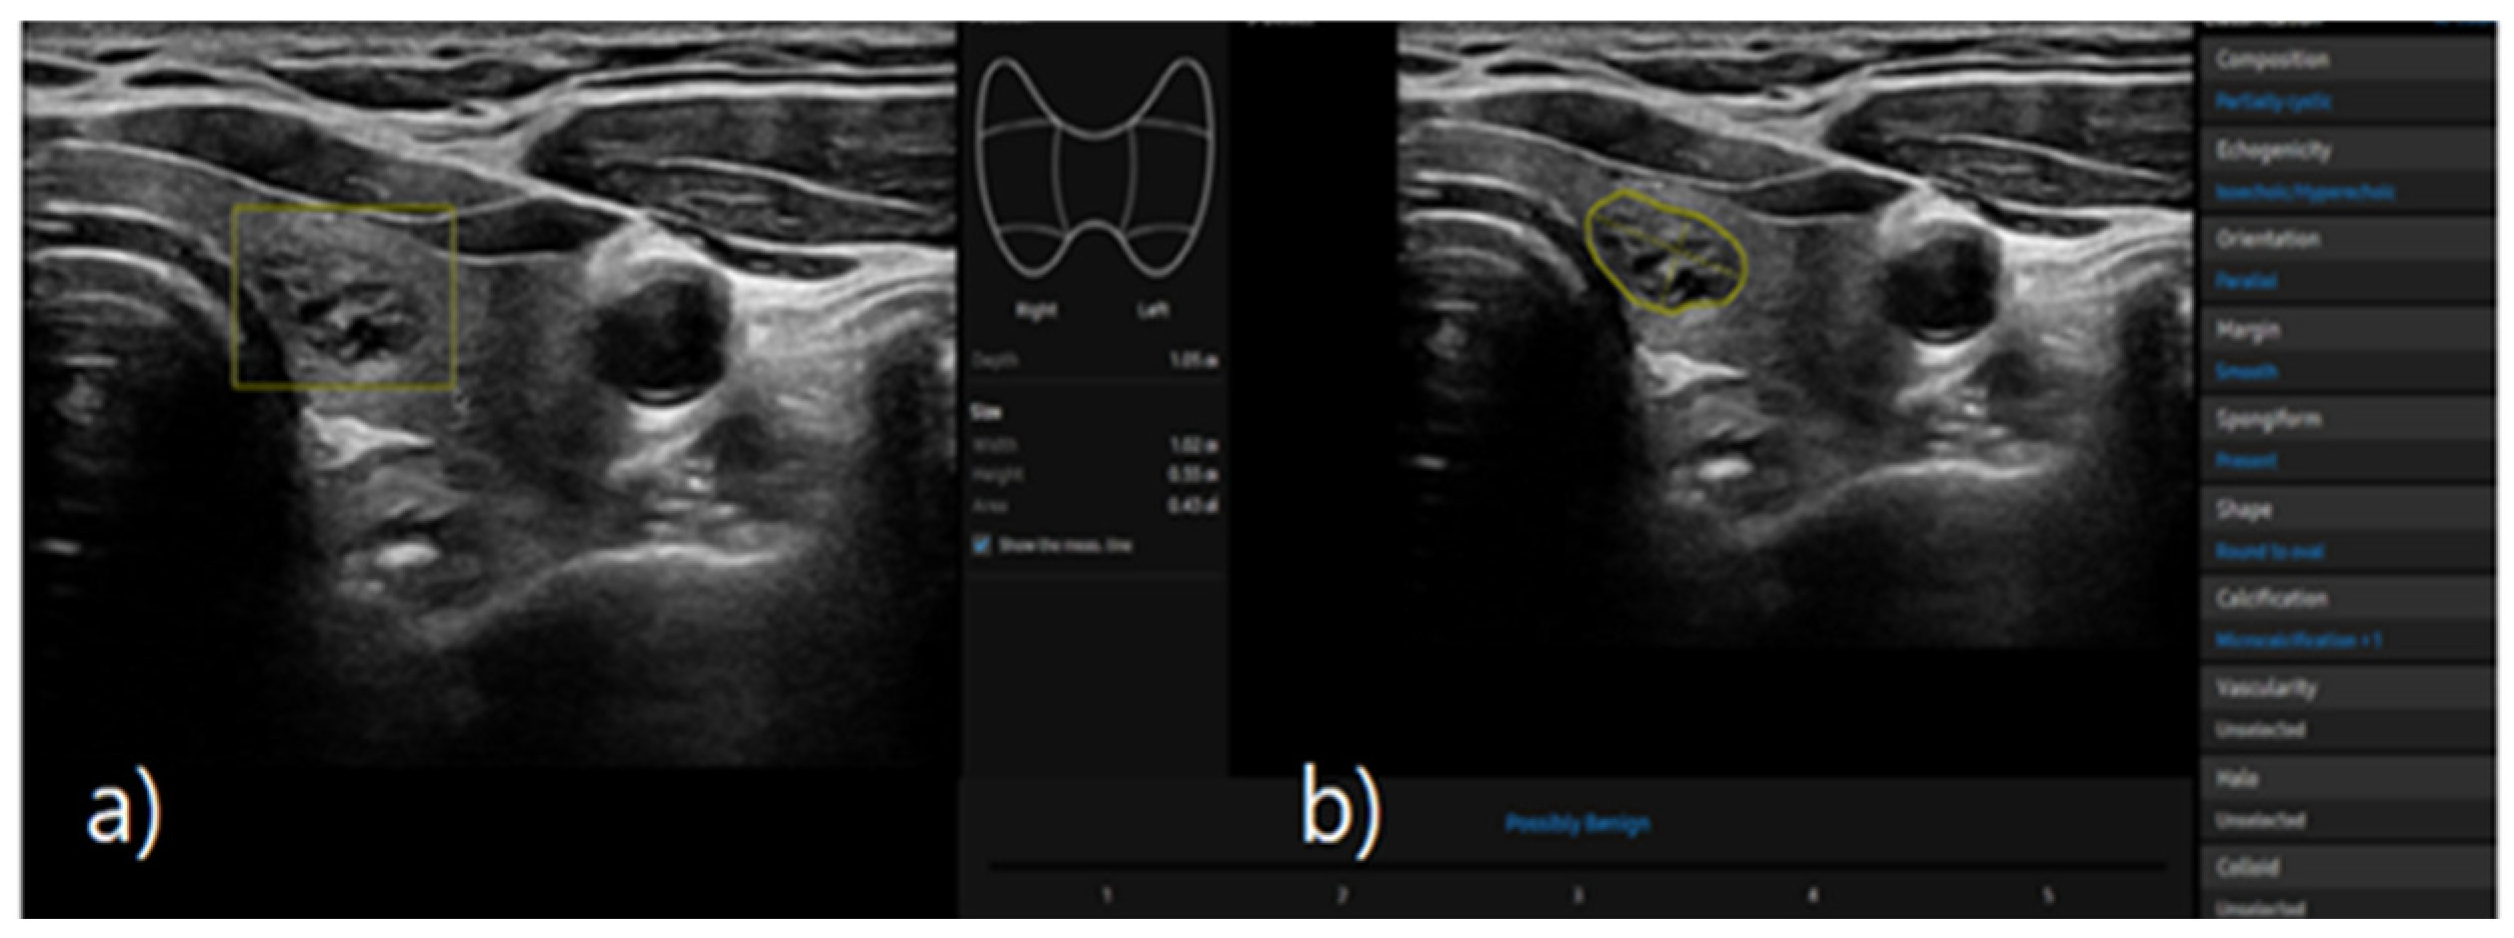

S-detect is an AI-based CAD software designed for ultrasound image analysis. Upon establishing the region of interest (ROI) for the targeted nodule, the software automatically delineates the boundaries and initiates the analysis [21,25]. If there errors the boundaries delineated by the software, manual delineation of the boundaries was performed. First of all, conventional ultrasound scanning was performed. After freezing of a static ultrasound image of the thyroid nodule, the ROI was manually set around the lesion, and S-detect was subsequently utilized to analyze the lesions. The nodules were then classified as “possibly benign” or “possibly malignant” based on characteristics such as internal composition, echogenicity, orientation, margin, and shape. All classifications rendered by S-detect (“possibly benign” or “possibly malignant”) were independently reviewed by an internal medicine specialist with over 20 years of experience in thyroid imaging. This procedure is depicted in Figure 3 and Figure 4.

Figure 3. a) Ultrasound grayscale transverse image of the left thyroid lobe in a 57-year-old woman. b) Thyroid nodule automatically classified as “possibly benign” using S-detect according to characteristics such as internal composition, echogenicity, orientation, margin, and shape.